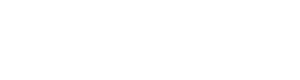

- Jo çdo dëmtim i meniskut duhet operuar.